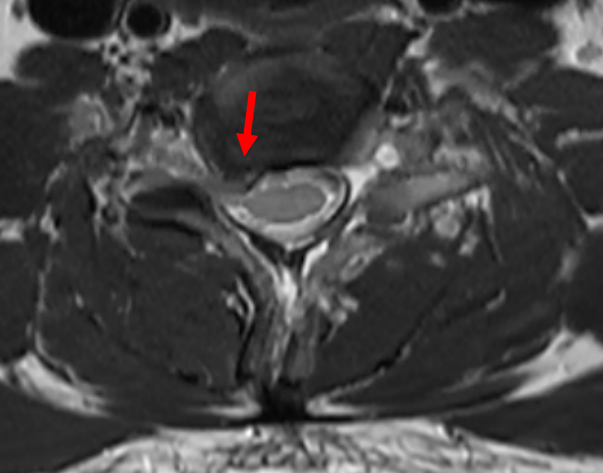

磁共振檢查發現頸椎間盤脫出

診斷神經根型頸椎病

紅色箭頭:頸椎間盤突出,

頸肩、上肢疼痛的“罪魁禍首”